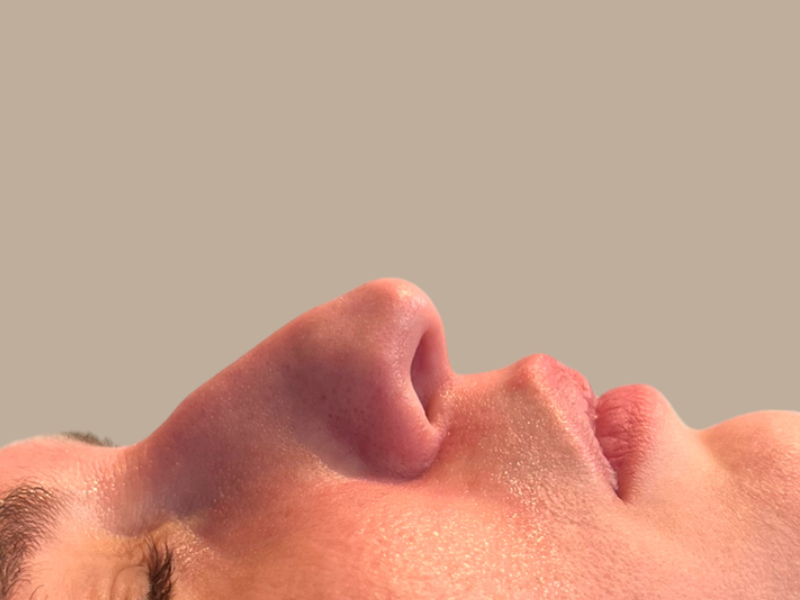

לפני ואחרי

לפניכם דוגמה למטופלות רשת מרפאות פרופורציה:

מהן תוצאות הטיפול?

על פי דר' לוין רופא אסתטיקה ותיק ומנוסה ברשת מרפאות פרופורציה "מתוך כל הטיפולים האסתטיים שאנו עושים בקליניקה, זה הטיפול שנותן באופן הכי משמעותי תחושת אושר מיידית לכל מטופל שמבצע אותו. האף מקבל מיד פרופורציות חדשות התורמות לאסתטיקה הכללית של הפנים. את התוצאה רואים כאמור מיד בסיום הטיפול והיא מאפשרת למטופל ליהנות מהרמוניה חדשה בפניו, אותה ניתן לתחזק אחת לתקופה".